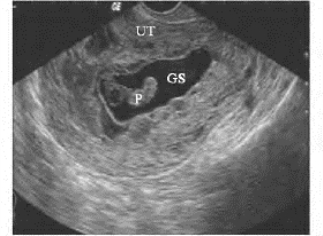

图34-10 过期流产声像图

孕4个月胚胎过期流产,P:胚胎组织;GS:羊水;UT:子宫